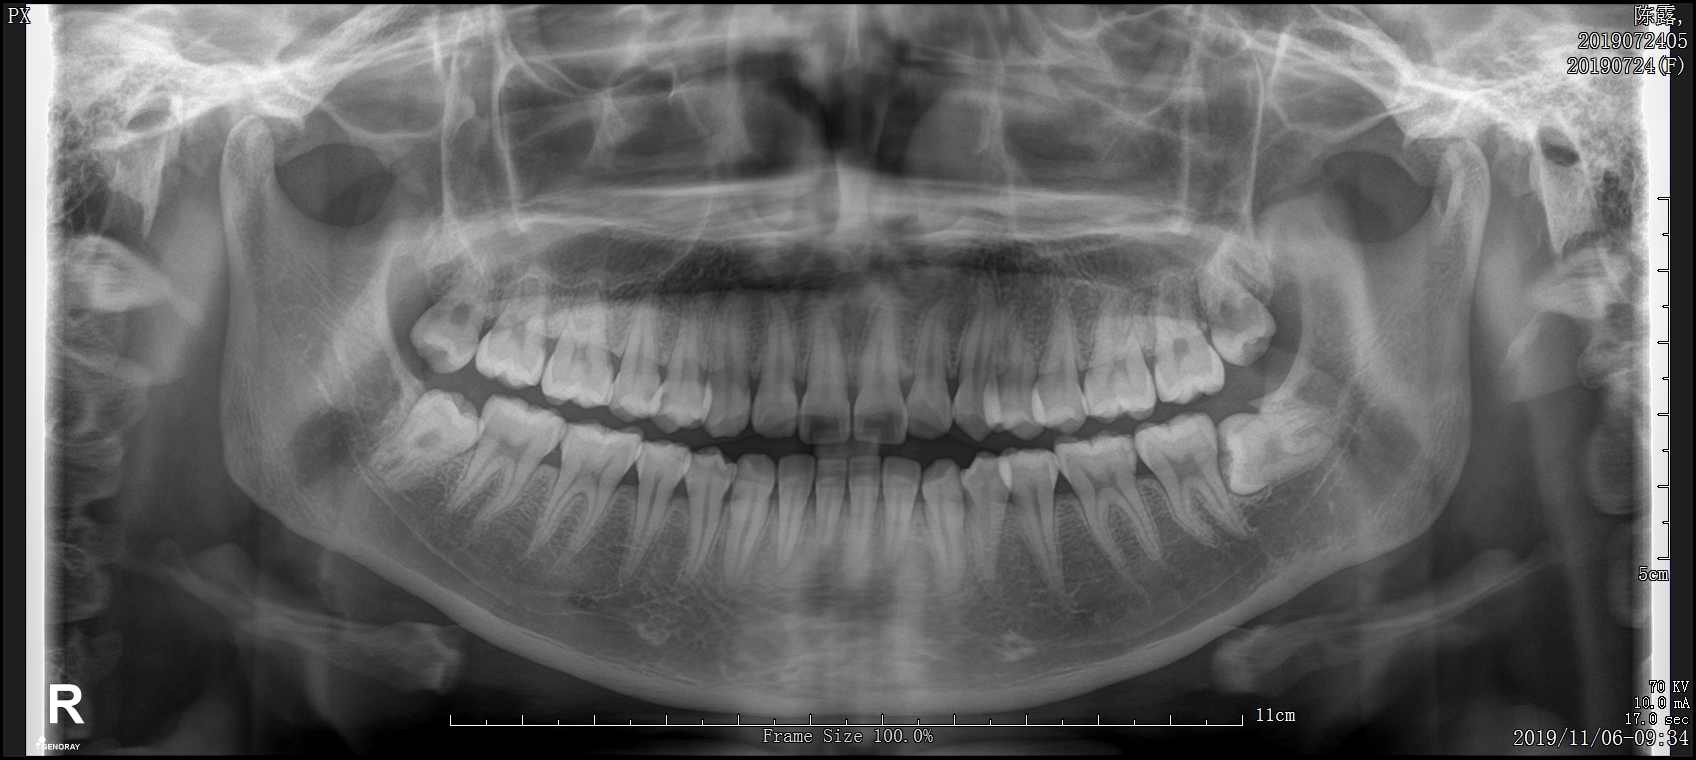

経口胆嚢造影は、胆嚢のX線検査です。胆嚢は、腹腔の右上、肝臓のすぐ下に位置する臓器です。肝臓によって生成される液体である胆汁を貯蔵し、食事からの脂肪の消化と吸収を助けます。

経口胆嚢造影検査は、胆嚢がんや肝臓の胆管系における胆汁の流れの減少または遮断など、胆嚢に関連する問題を診断するために使用されます。

経口胆嚢造影検査は、起きている間に外来処置として行うことができます。胆嚢の収縮と胆汁の放出を刺激するために、特別な高脂肪飲料が与えられる場合があります。これは医師が問題を特定するのに役立ちます。

医師は通常、診察台に横になるように指示しますが、立っていただくよう指示される場合もあります。これは、胆嚢のどのようなビューが必要かによって異なります。次に、透視装置と呼ばれる X 線カメラを使用して胆嚢を観察します。部屋の設定によっては、医師が見ている内容をモニターで確認できる場合があります。医師は検査中ずっと X 線検査を行います。